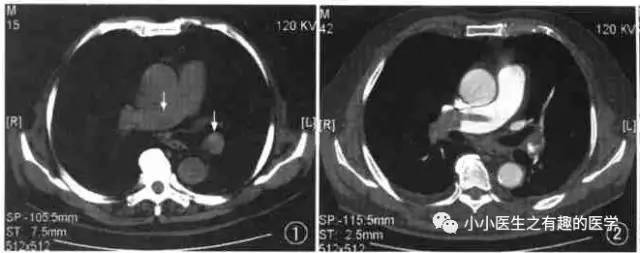

2004年,李铁一教授就说了:对于不能使用对比剂或因非典型心肺症状而仅作平扫的病例, 肺动脉CT 平扫的异常密度改变能提示急性肺动脉栓塞的存在。

国外有高手专门研究了CT平扫诊断肺栓塞的可靠程度。

高分辨CT平扫管腔内高密度征象诊断肺栓塞的敏感性36.0%, 特异性99.0%, 阳性预测值90.0%, 阴性预测值85.6% 。

阴沟里洗原文:The hyperdense lumen sign has an over-all sensitivity of 36.0%, specificity of 99.0%, PPV of 90.0%, and NPV of 85.6% (κ = 0.449; P-value < 0.001).

高分辨CT平扫管腔内高密度征象诊断中心肺栓塞敏感性66.7%, 特异性99.1%。

阴沟里洗原文: In detecting central thromboembolism, the sensitivity, specificity, PPV, and NPV of this sign were 66.7, 99.1, 88.9, and 96.4%, respectively (κ = 0.740; P-value < 0.001).